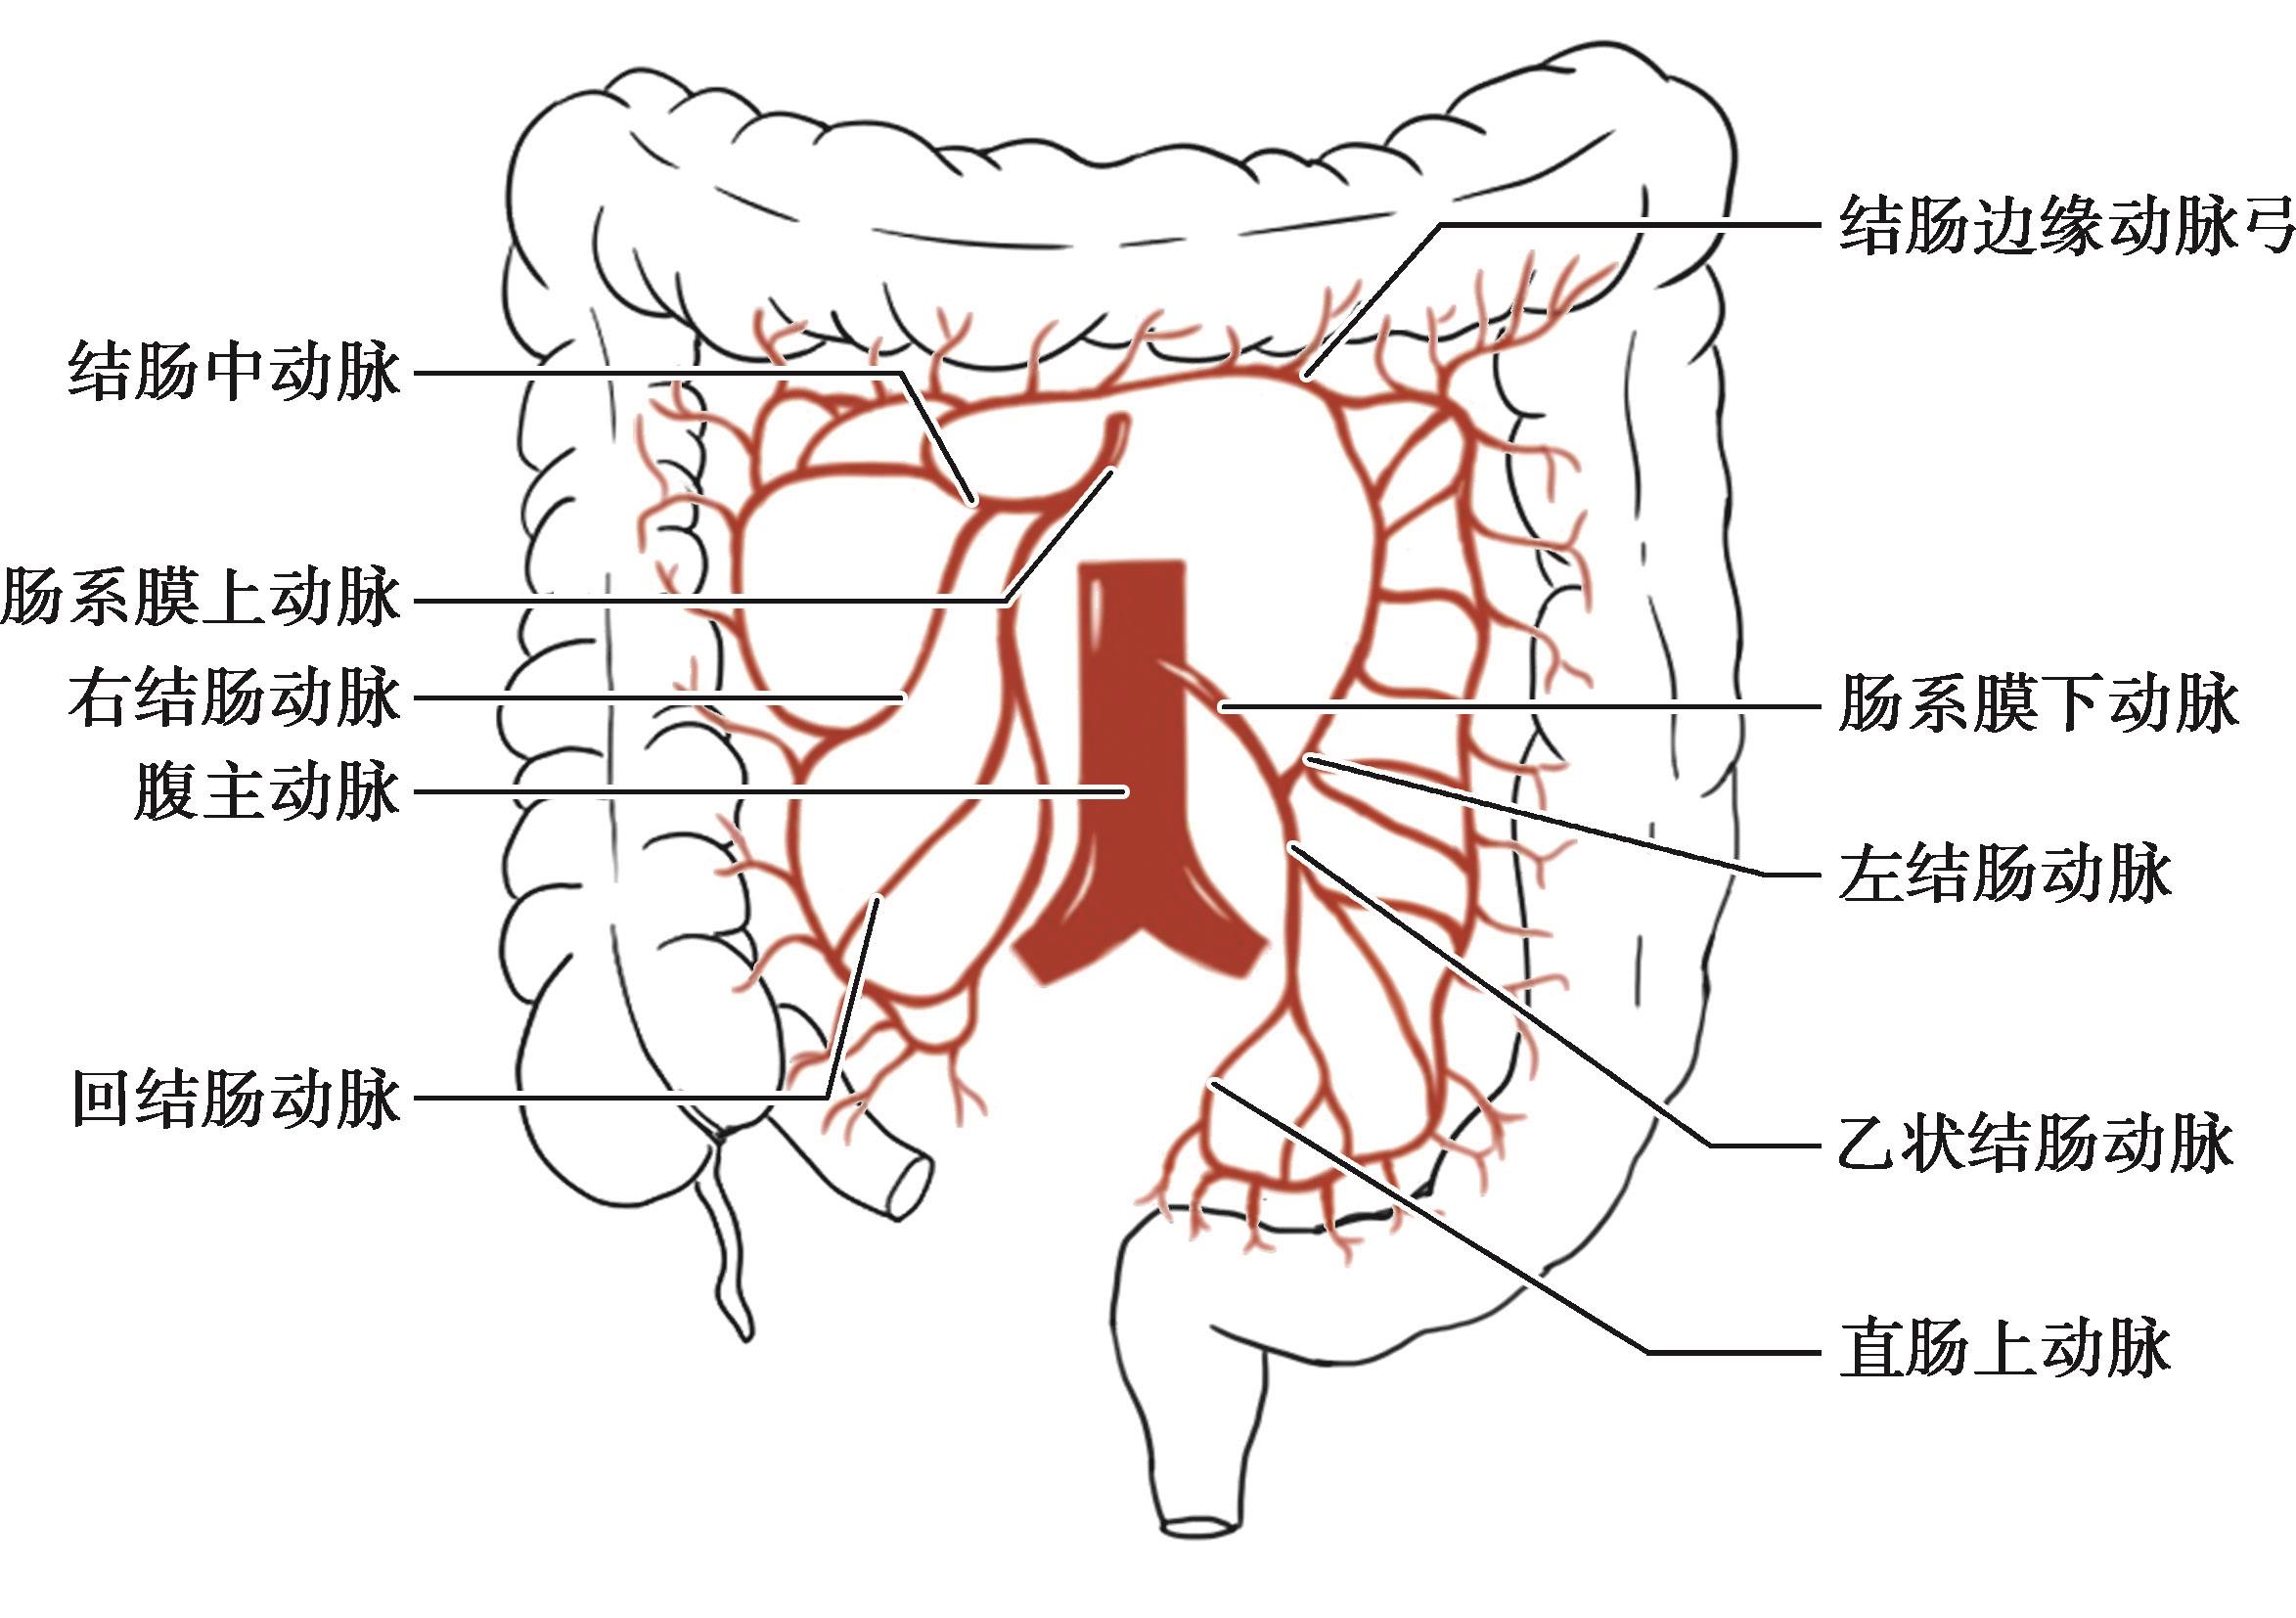

一般来说,横结肠、肝曲、升结肠、盲肠的血液供应来自肠系膜上动脉分出的结肠中动脉、右结肠动脉和回结肠动脉,而降结肠、乙状结肠则由肠系膜下动脉分出的左结肠动脉和乙状结肠动脉供血(图2-5)。

图2-5 结肠的动脉血供

主要起源于肠系膜上动脉,但极少数也可起源于腹腔动脉、肠系膜下动脉或直接起自腹主动脉,主要分支分布于横结肠。结肠中动脉一般距胰腺下缘1cm处单干起源于肠系膜上动脉的右侧壁,极少数结肠中动脉缺如,也有双干或3干者,也有与右结肠动脉共干者。结肠中动脉发出后,越过十二指肠水平段的前方,于右上方进入横结肠系膜。根据分支的高低及分支间的吻合情况,可将单干结肠中动脉分为3型。

Ⅰ型:在横结肠系膜内分出2支或3支,形成1~3级动脉弓,右支分布于横结肠右1/3和结肠肝曲,左支横贯横结肠系膜,分布于横结肠左2/3,并与左结肠动脉升支吻合。

Ⅱ型:发出后立即分出左右两支,右支分布于横结肠右半,左支分布于横结肠左半。

Ⅲ型:发出后向右上方走行到横结肠边缘才分出左右支,在分支间缺乏动脉吻合。

结肠中动脉与其他结肠动脉常有吻合:①右支与右结肠动脉的升支在肝曲处吻合;②右支与回结肠动脉的结肠支吻合;③左支与左结肠动脉的升支吻合;④左支与副结肠中动脉吻合。所以,当术中不慎损伤结肠中动脉时,不一定会影响其血供,要仔细观察肠管颜色,以决定是否要进行肠段切除。

若由肠系膜上动脉发出双干的结肠中动脉时,其中走向左侧的一支成为副结肠中动脉;副结肠中动脉有时与右结肠动脉共干,其左右分支分别与左结肠动脉升支和结肠中动脉左支吻合。有副结肠中动脉的患儿,手术损伤结肠中动脉左支时对横结肠血供影响不大,但这种吻合使得横结肠系膜左侧的无血管区变小,故在行胃空肠吻合或胆肠Roux-Y吻合时应注意。

在结肠中动脉起点下方起自肠系膜上动脉,或与结肠中动脉共干起始,经腹后壁腹膜深面右行,在靠近升结肠左缘处分为升、降支。升支上行与结肠中动脉右支吻合;降支下行与回结肠动脉的上干吻合。该动脉发出小支分布于升结肠上2/3部和结肠肝曲。

为肠系膜上动脉发出的第3个分支,主要分支分布于末端回肠和盲肠;与右结肠动脉和回肠动脉分支均有吻合。

肠系膜下动脉在L 3 水平于腹主动脉前壁发出,走行1~3cm后分出左结肠动脉、乙状结肠动脉和直肠上动脉。

为降结肠的供血动脉,一般为1支,由肠系膜下动脉发出,随后分出升支和降支。升支可越过脾曲与结肠中动脉的左支吻合;降支向下走行与乙状结肠动脉的分支吻合。该动脉极少起自肠系膜上动脉,也可能与乙状结肠动脉共干,亦有缺如者由副结肠中动脉左支代替。

为肠系膜下动脉的第二分支,少数亦可由左结肠动脉分出,随后分出升支和降支。升支与左结肠动脉的降支吻合;降支与直肠上动脉的分支吻合。

是从回结肠开始,沿着升结肠、肝曲、横结肠、脾曲、降结肠和乙状结肠的内侧缘到直肠上端的各结肠动脉分支之间相互吻合而形成的动脉弓(图2-5),实现了肠系膜上、下动脉的相互交通,该动脉弓位于结肠系膜内。肥胖者系膜脂肪组织厚,动脉弓埋于其内难以被发现,但有由动脉弓发出的边缘动脉支分布于各肠段的肠壁,因此,进行结肠肠段切除时应注意保护边缘血管。有5%~10%的病例在结肠脾曲处左结肠动脉与横结肠动脉之间无吻合支,故在常见型HD拖出术时,离断肠系膜下动脉前应先阻断血流观察降结肠血供情况。